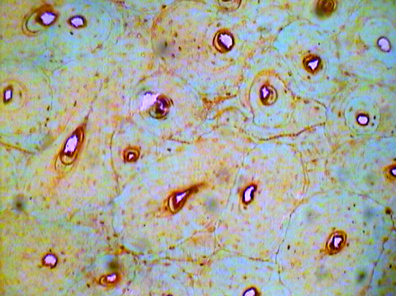

Cells